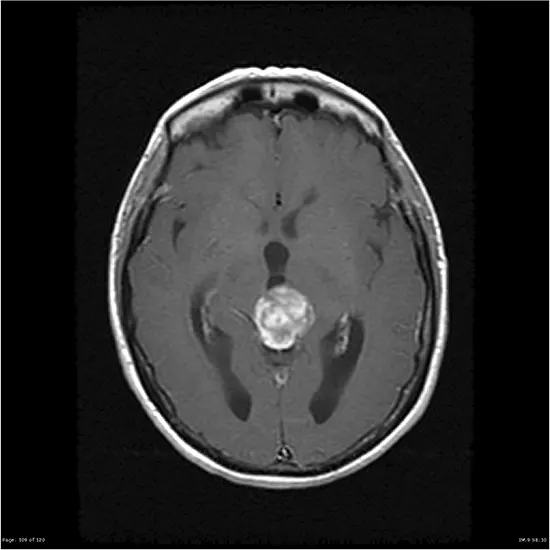

- Imaging tests: Imaging exams such as MRI or CT scans are frequently used to visualize intelligence and notice the presence of a pineal astrocytoma.

These assessments can assist decide the dimension and place of the Tumour, as nicely as its relationship to nearby constructions in the brain.